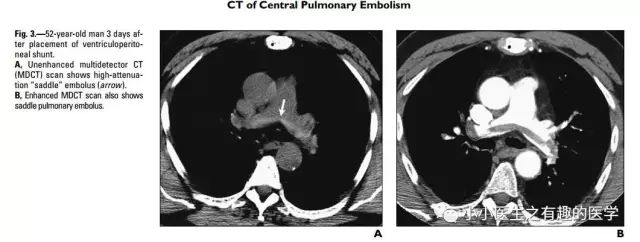

作者单位:Department of Radiology, University of Washington MedicalCenter, University of Washington School of Medicine(华盛顿医科大学)。

老外报道一例患者,门诊急诊CT平扫发现肺栓塞,但是患者危重,再次外出做增强CT很危险,别人直接高分辨CT诊断肺栓塞,直接治疗,病情缓解再出去检查。在中国,你懂的(抱歉:有些文献*载下**要钱,穷,没有*载下**到)。

文献五

国外有高手专门研究了CT平扫诊断肺栓塞的可靠程度。

高分辨CT平扫管腔内高密度征象诊断肺栓塞的敏感性36.0%, 特异性99.0%,阳性预测值90.0%,阴性预测值85.6% 。

高分辨CT平扫管腔内高密度征象诊断中心肺栓塞敏感性66.7%, 特异性99.1%。